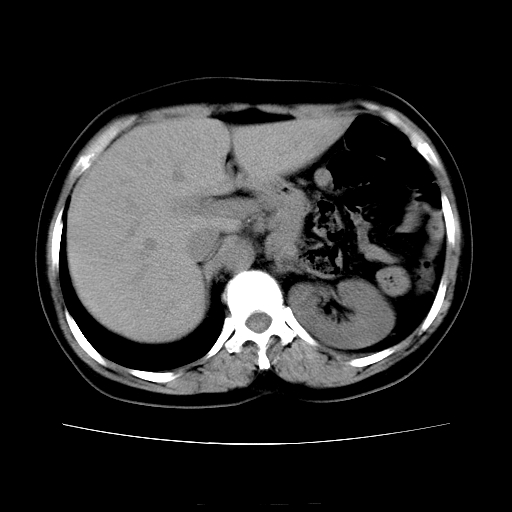

女45y多次(7次)碎石,结果不理想!曾碎石后尿出小碎石,仍腰痛,要求ct,其它不详.本人更倾向于钙化斑!无肾实质破坏,积水等提示集合系统无梗阻.另外腹腔多处钙化.是否结核后改变!谢谢赐教!

1)双肾结石。2)脾脏钙化灶。3)腹膜后多发淋巴结钙化。

尿路结石与腹部淋巴结钙化共存,建议v尿路造影检查,免得钙化灶冤枉为结石受罚。

考虑双肾结石,肾脏实质无破坏表现,没有结核病史,不考虑肾结核,